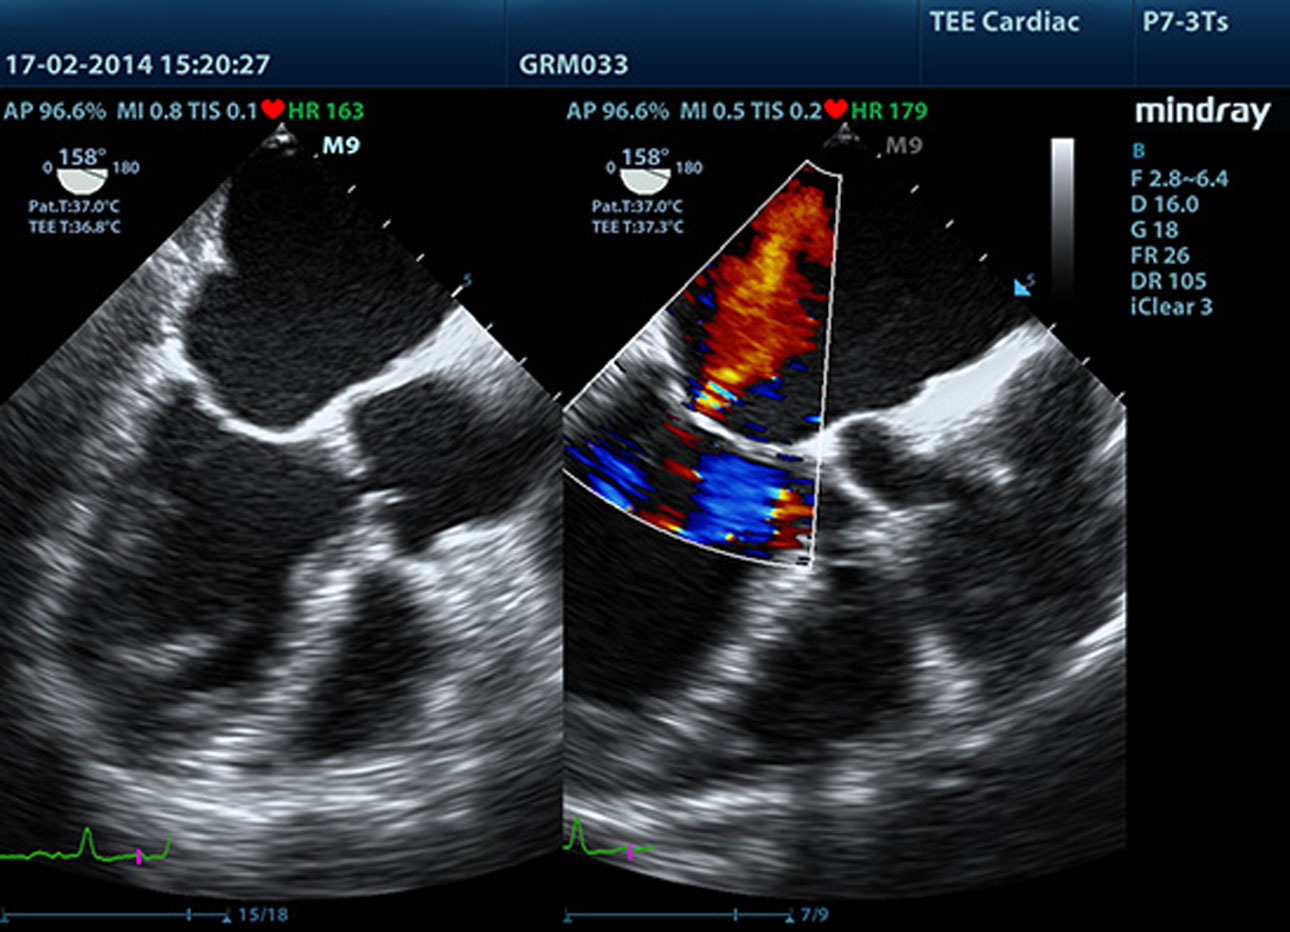

LVO with Stress Echocardiography

M9ŌĆÖs premium capabilities allow for LV opacification during stress, enhancing discrimination between myocardial tissue and blood pool, providing better visualization of the endocardial surface. Stress Echo feature on M9 includes a complete package for pharmacological stress and exercise stress echo. The package is supported by a flexible reporting system that can be optimized for your individualistic needs.